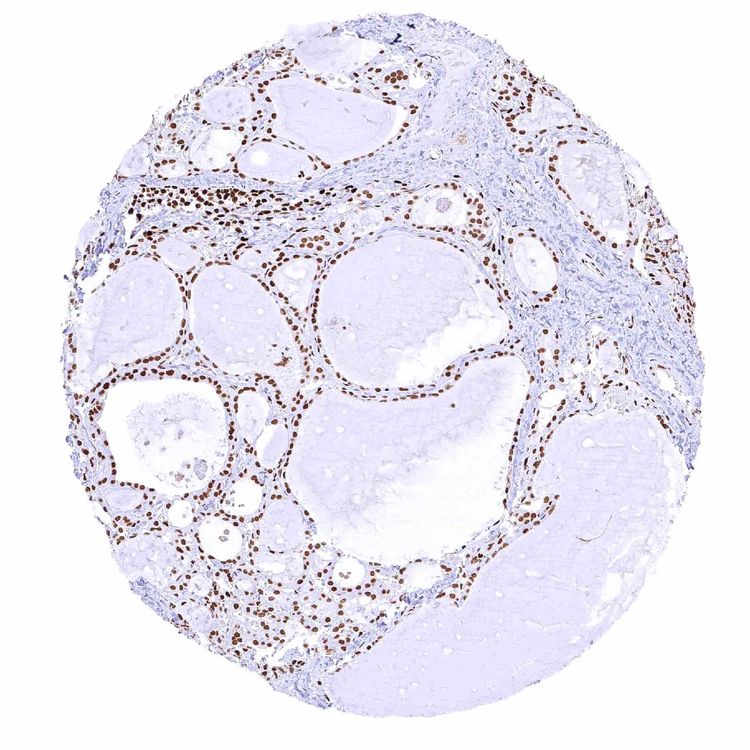

Thyroid gland